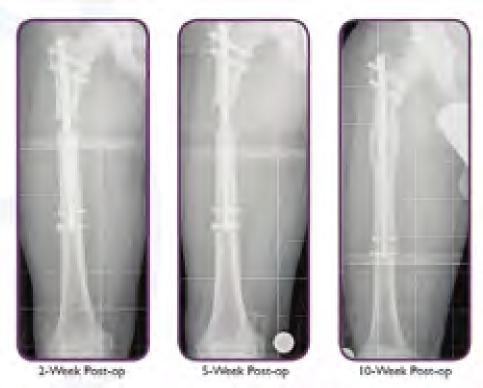

S.D. is a 2-year-old female who presented to the Orthopaedic Center at Dayton Children’s for an LLI noticed by the family. Her birth and developmental history were unremarkable and there was no family history of limb deformity. Examination revealed an LLI by tape measure and blocks of 2.5 cm left longer than right. She had hyperpigmentation involving her trunk, abdomen and left leg. Her neurovascular exam was normal, and she had hemi-hyper-trophy on her left calf with 2.5 cm increase in growth compared to the contralateral leg. A scanogram was obtained which showed a 3 cm overall limb length inequality with 2.0 cm difference in the tibias. Genetics was consulted verifying diagnosis of Klippel-Trenaunay-Weber syndrome. MRI of her brain and cervical, thoracic lumbar spine revealed no abnormalities. By age 6, her exam revealed a progressive discrepancy showing a 7.0 cm LLI; thus she had her first limb lengthening using a spatial frame external fixator and obtaining 5 cm of length, 20 percent of the length of her tibia (Figure 6).

During her lengthening of the tibia, she developed an equinus contracture on the lengthened leg requiring a percutaneous heel cord lengthening upon removal of the frame.